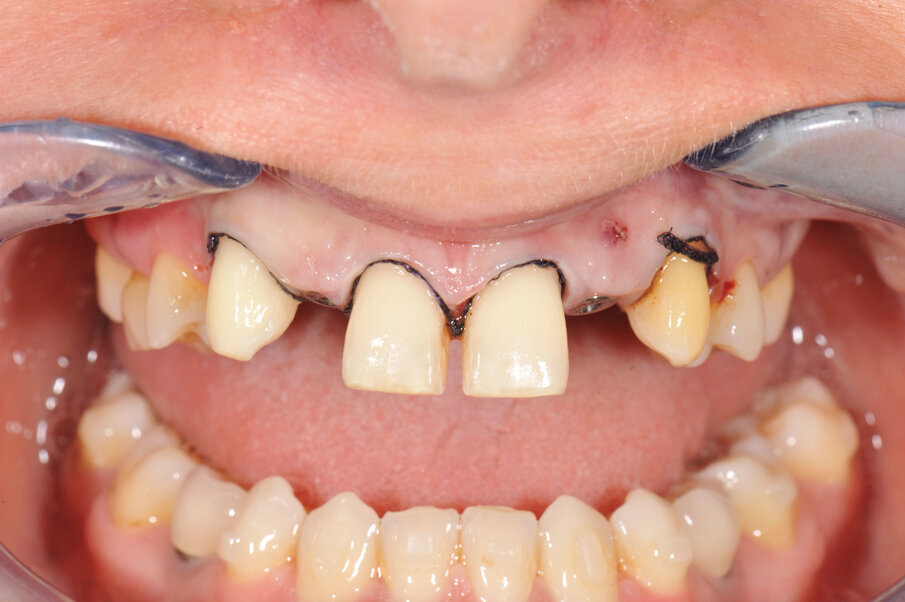

In deze casus is indertijd voor tissue level-implantaten gekozen en na ongeveer achttien jaar in functie is de esthetiek, mede door de vorm van de cuspidaten en het zichtbaar worden van de implantaten, discutabel te noemen (afbeelding 1 en 2).

In samenspraak met de patiënte en in goed overleg met de behandelend orthodontist werd besloten de implantaten op de posities 13 en 23 te verwijderen, de cuspidaten naar distaal te verplaatsen en de angulatie van de elementen te corrigeren, zodat het plaatsen van twee implantaten op de posities van de laterale incisieven goed mogelijk zou worden (afbeelding 5 en 6).